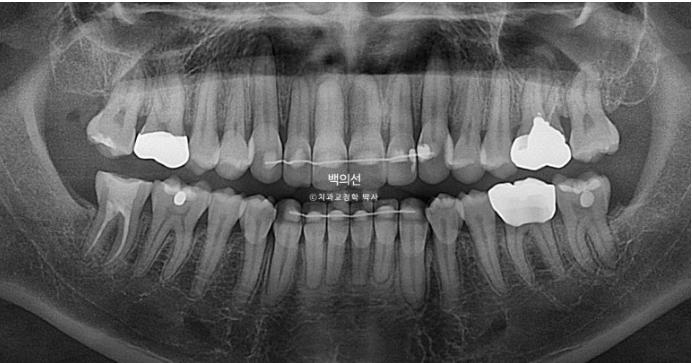

The orthodontic result shows good root parallelism.